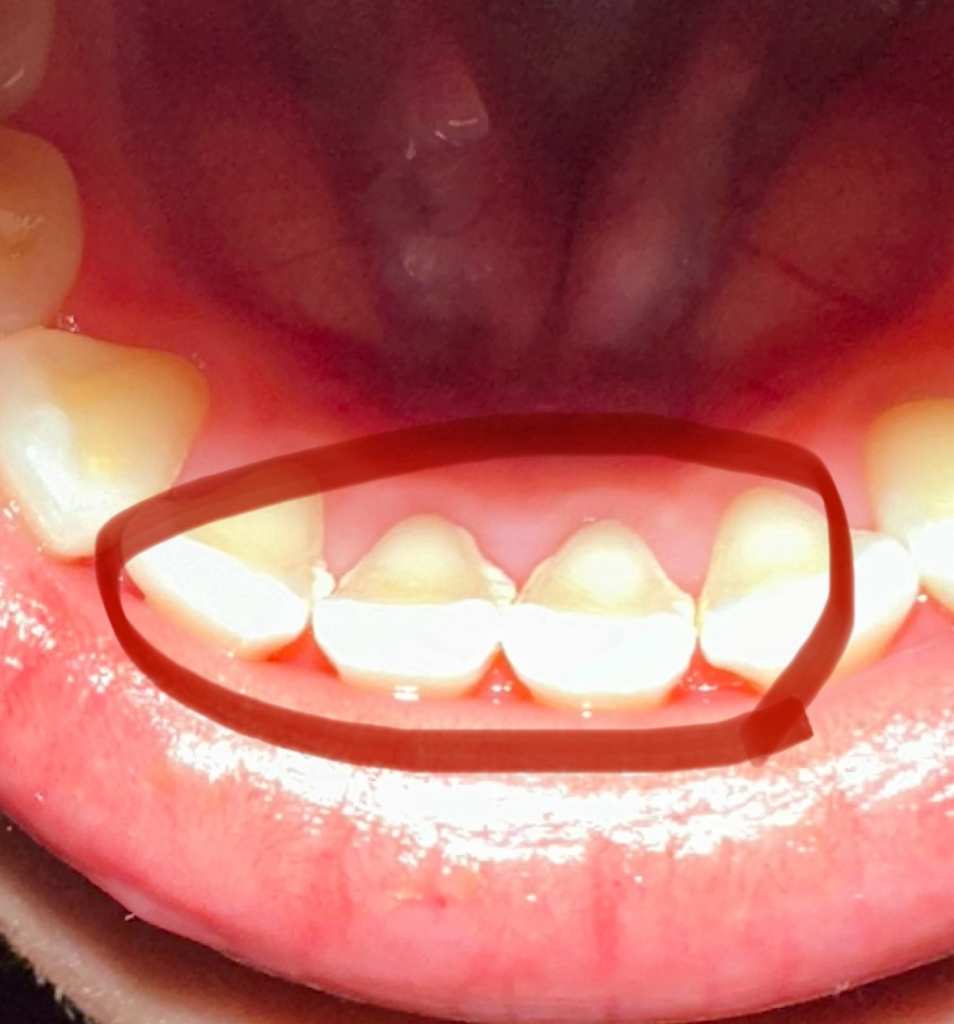

치석 관련해서 질문 드립니다!

보시다시피 치석이 좀 심한편인데 제가 치과 방문을 1주일 뒤에 가능할거같은데 그동안 더 심해져서 잇몸이 내려앉거나 충치가 생기거나 그럴까요??

• 1번 째 사진